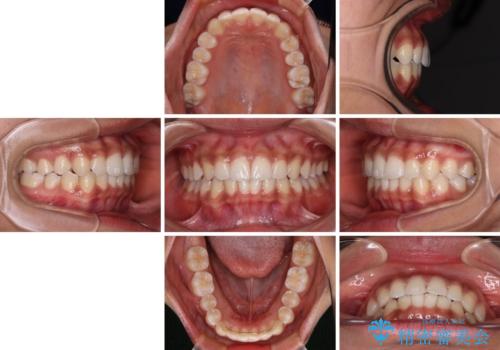

- 8ヶ月

- 上下前歯の叢生を気にして来院された患者様です。

インビザラインでの治療を希望されていて、デコボコの程度が中等度であり、安価なパッケージにて対応可能と判断されたため、インビザライン・モデレートを用いて矯正治療を行うこととしました。

インビザライン・モデレートは、製作できるアライナーの枚数に制限があるため、移動可能な量に限りがあるものの、インビザライン・ライトよりも枚数が多いため、幅広い症例に対応可能です。